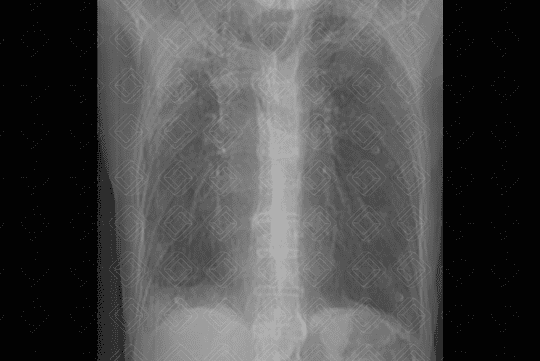

Descrição das figuras 1 e 2: Radiografia de tórax PA e perfil evidenciando os sinais clássicos de doença pulmonar obstrutiva crônica: diafragma retificado, coração alongado e verticalizado, além de aumento anteroposterior da caixa torácica.

• Radiografia de tórax: O r endimento da avaliação da DPOC pelo estudo radiológico simples é bastante limitado, não havendo anormalidade na radiografia se não existir aprisionamento de ar. Quando há aprisionamento de ar, os critérios mais seguros são: diafragma rebaixado ou retificado; aumento do espaço retroesternal (maior que 3 cm) e persistência do aumento do espaço retroesternal na expiração, coração alongado e verticalizado, presença de bolhas é inferida pela identificação de área de maior radiotransparência, avascular, podendo ou não estar delimitada por fina linha branca (figuras 1 e 2) ;